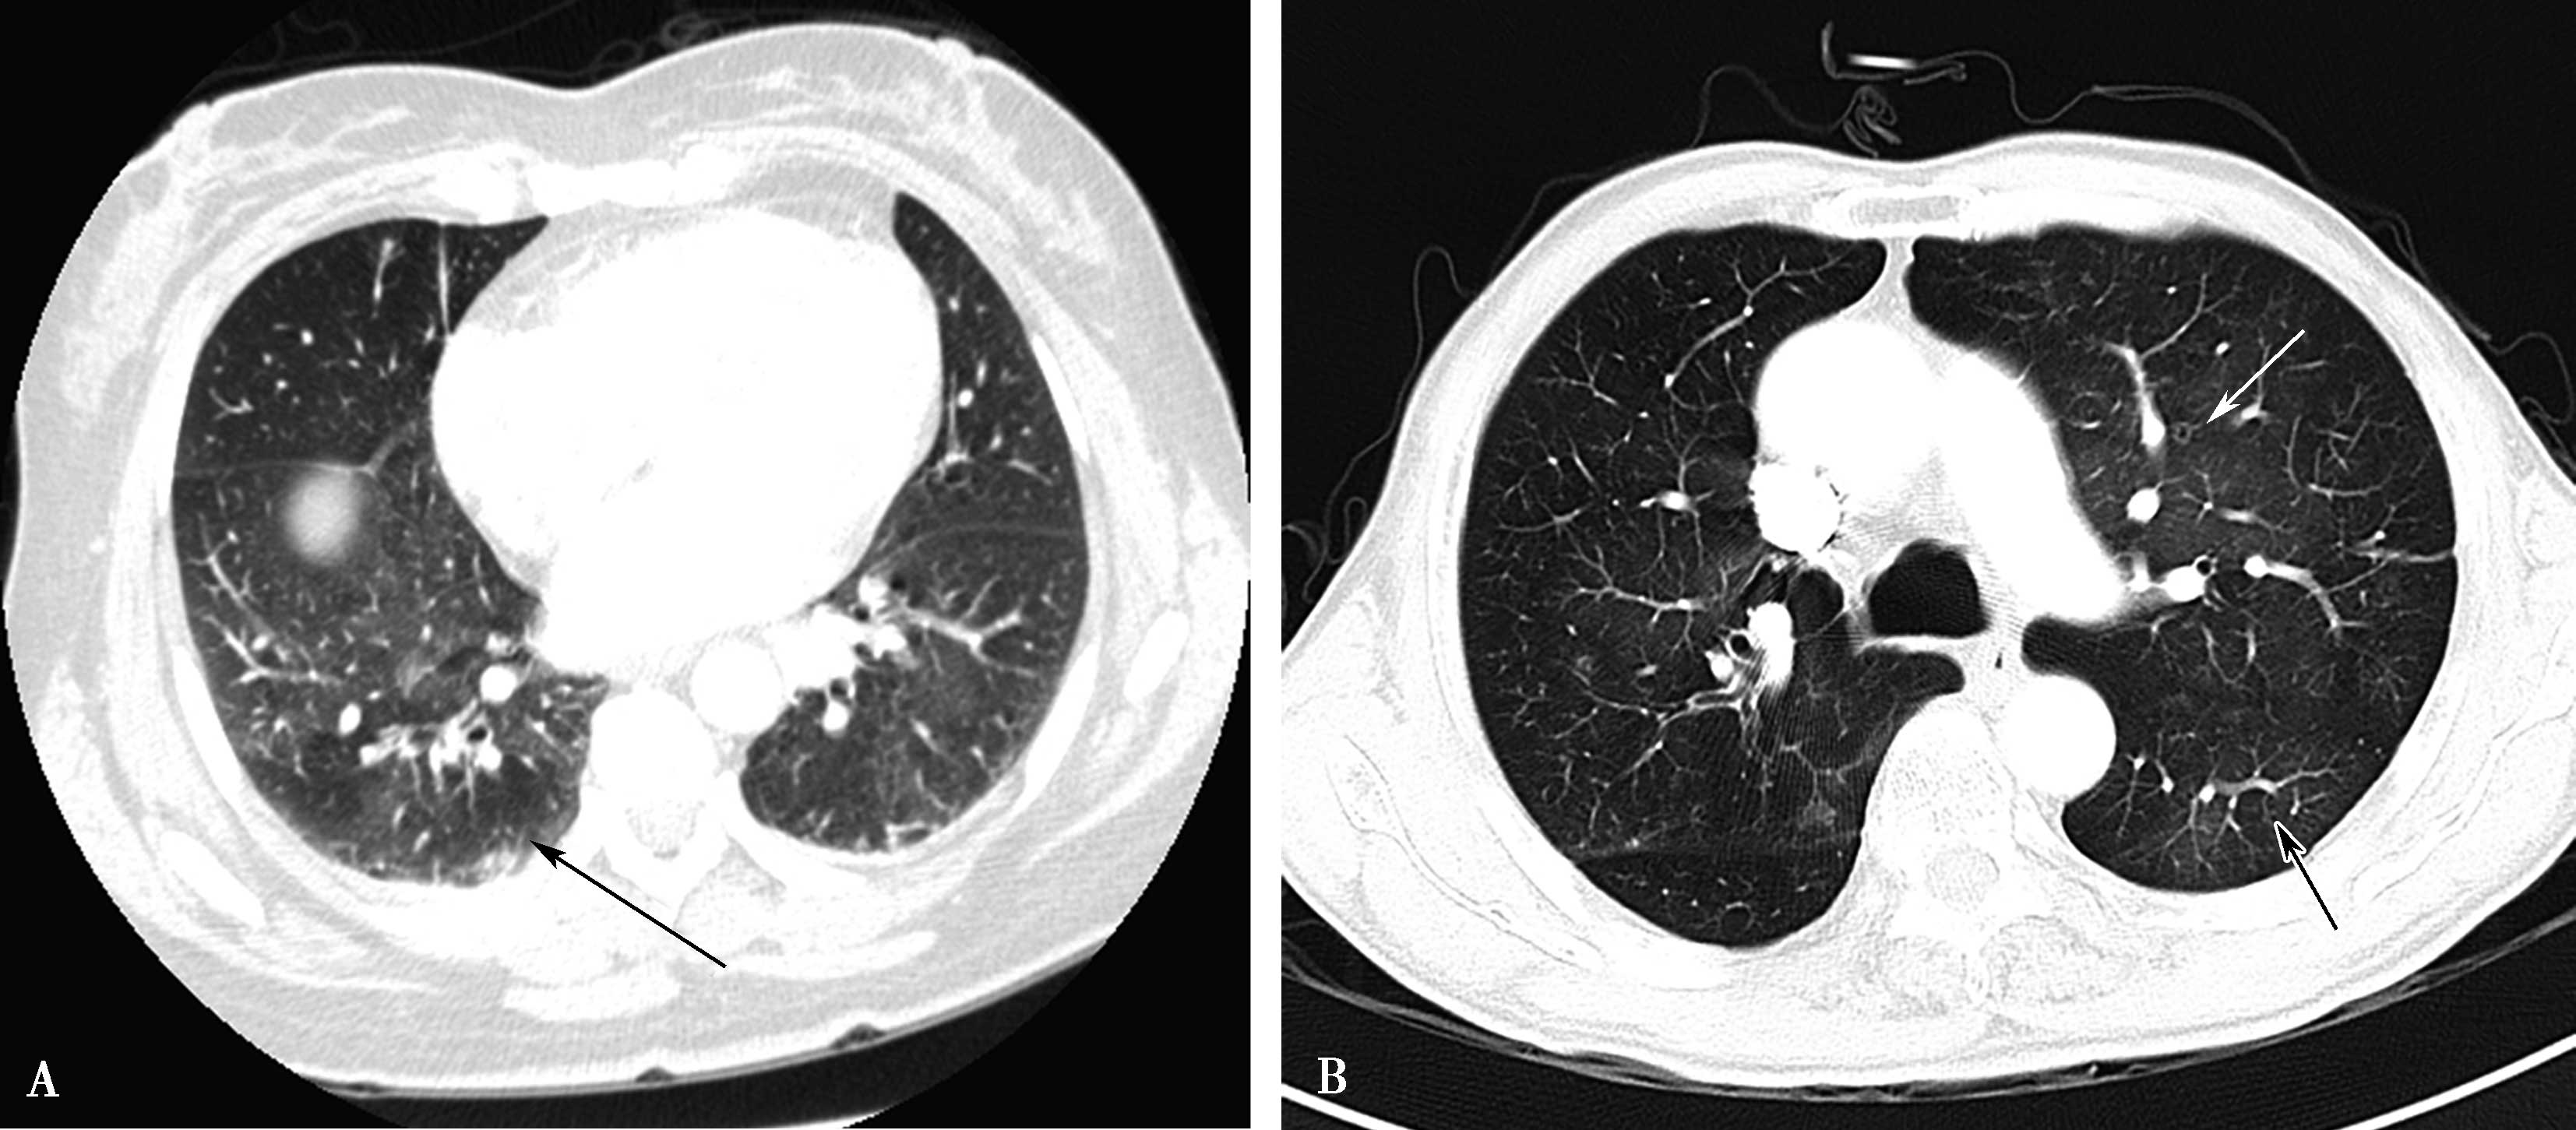

由于血栓栓塞造成栓塞血管区血流灌注减少,与过度灌注区形成明显密度差,造成 “黑白相嵌”现象,称为 “马赛克征”。此为非特异征象,小气道病变亦可形成此种征象(图8-4-4)。

图8-4-4 急性肺栓塞间接征象

A.马赛克征,黑白相间(↑);B.马赛克征,白箭显示相对灌注较好区域,黑箭显示灌注较差区域,呈黑白相间(↑)

图8-4-5 急性肺栓塞的间接征象

A.多层重组,右肺上叶肺栓塞,血管闭塞,肺梗死,呈三角形实变影(↑);B.两周后,横断图像示右肺上叶前段肺栓塞肺梗死空腔形成(↑)